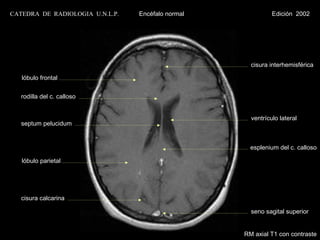

CATEDRA DE RADIOLOGIA U.N.L.P.   Encéfalo normal             Edición 2002

cisura interhemisférica

lóbulo frontal

rodilla del c. calloso

ventrículo lateral

septum pelucidum

esplenium del c. calloso

lóbulo parietal

cisura calcarina

seno sagital superior

RM axial T1 con contraste

lóbulo parietal                                 seno sagital inferior

RM axial T2